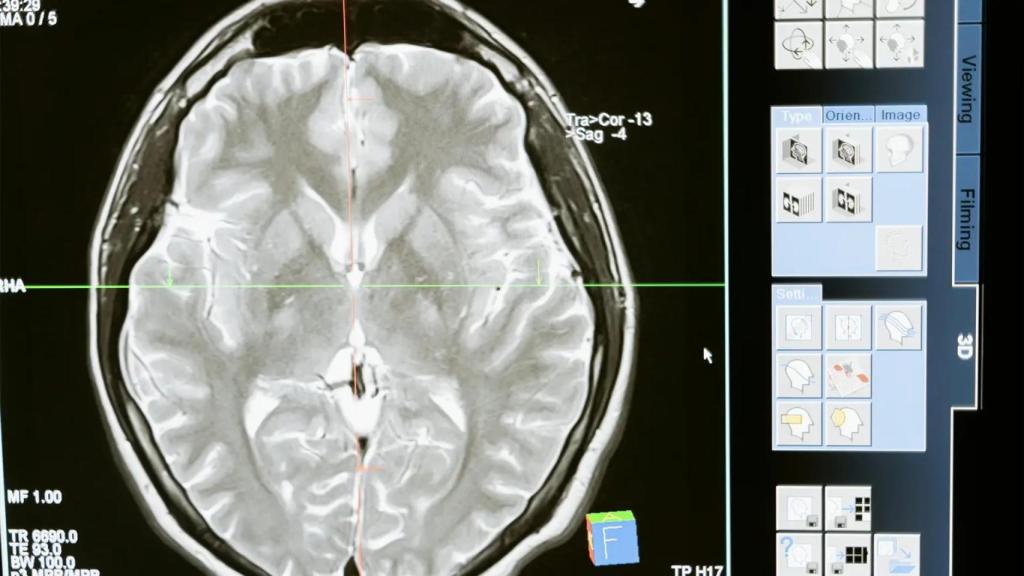

Se trata de una terapia génica, la primera que se prueba con estos pacientes, que se administra con una cirugía cerebral que dura entre 12 y 18 horas.

La enfermedad de Huntington se describió en el siglo XIX. El gen que la causa se descubrió hace tres décadas. Ahora, una terapia —de nombre AMT-130— ha logrado ralentizar su progresión por primera vez.

Este porcentaje supone que el deterioro que normalmente se esperaría en un año se retrasaría hasta cuatro con el tratamiento, que se administra en una cirugía cerebral que dura entre 12 y 18 horas.

En el caso de que suceda, sospecha que el principal reto será cómo conseguir que se pueda extender su uso, puesto que se administra directamente en el cerebro mediante una intervención neuroquirúrgica.

Para ello, han recurrido a "centros de excelencia en EEUU, Cardiff y Varsovia". Pero habría que encontrar una mejor forma de hacer esta cirugía para que sea "rápida, eficiente y de una manera rutinaria".